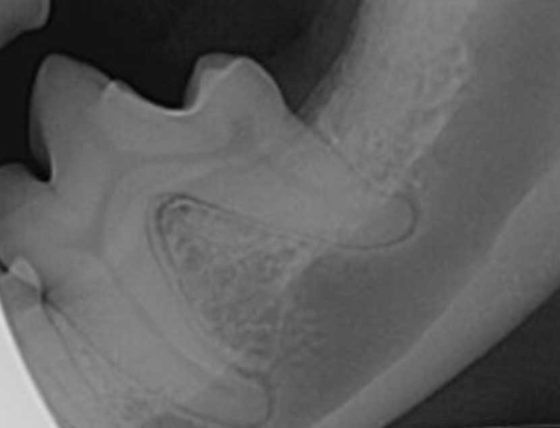

Figure 4. Dental radiographs of left and right mandibular first molar teeth in a five-year-old dog with moderate periodontal disease. The mandibular second molar teeth were extracted and open root planing performed on the distal aspect of the distal roots of the first molar teeth. The owner was very motivated to salvage the teeth and committed to twice-daily brushing.